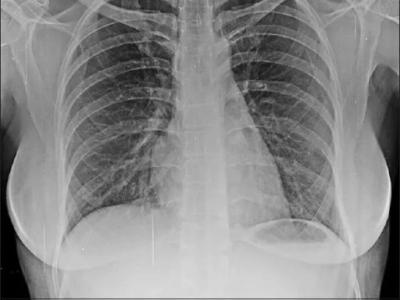

28 biomarkers studied in 259 SSc-ILD, 179 SSc-NO ILD, 172 IPF & 30 healthy controls. Composite biomarker index (w/ SP-D [surfactant prot. D], Ca15-3 [MUC1], & ICAM-1) strongly correlated w/ SSc-ILD (adj OR 12.7); independent of age, sex, smoking, PFTs https://t.co/F0iKFqcZoY https://t.co/Ao25N1DFIx